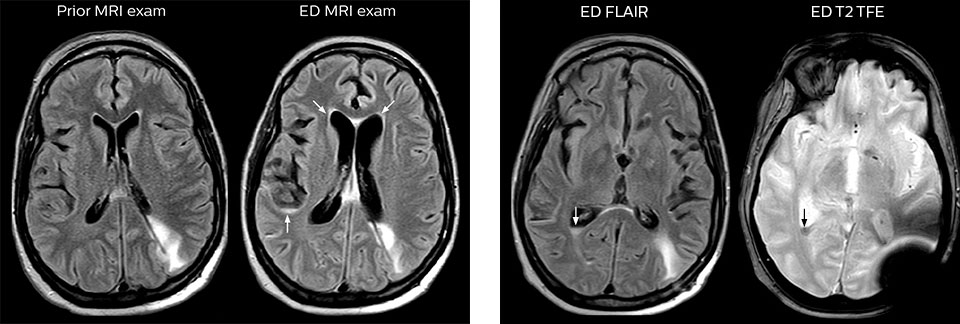

Dieser Patient wurde mit Kopfschmerzen vorstellig, die sich bei einer Flexion des Nackens verschlimmerten, und wir sehen hier eine Chiari-Malformation vom Typ I mit niedrig liegenden Kleinhirntonsillen sowie degenerativen zervikalen, thrombolytischen Veränderungen.

Eine Reihe von Protokollen wurde ausgearbeitet, um sicherzustellen, dass überweisende Ärzte die am besten geeignete MRT-Untersuchung anfordern. Die optimierten MRT-Protokolle umfassen auch die kontrastmittelverstärkte 3D-Bildgebung, die es den Neurochirurgen ermöglicht, während eines stereotaktischen Eingriffs im OP komfortabel auf die isotropen Daten zuzugreifen.

Nach der MRT-Untersuchung werden die vorläufigen Berichte den überweisenden Ärzten schneller als zuvor bereitgestellt, weil dies den Anforderungen der Ärzte entspricht, die Entscheidungen zur Behandlung des Patienten treffen müssen. Die Nutzung eines neu konzipierten Berichterstellungsprozesses führt zu Gesamtdurchlaufzeiten, die denen von CT-Untersuchungen ähneln. Eine weitere, neu eingeführte Änderung besteht darin, dass MRT-Sicherheits-Screening-Daten aus dem Krankenhaus-Informationssystem abgerufen werden, was circa 30 Minuten einspart.